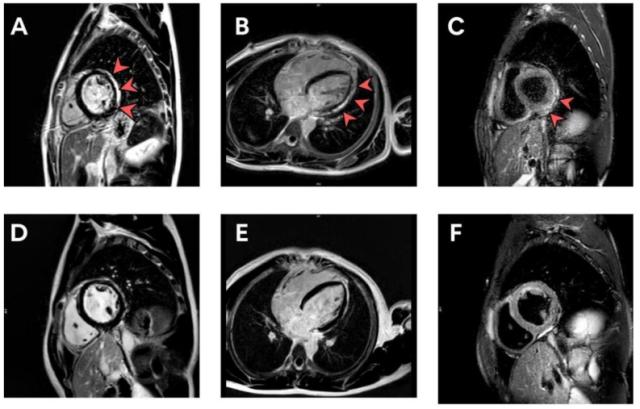

Le manifestazioni cardiovascolari sono state osservate nel 29,24% dei pazienti, con sintomi che variavano dalla tachicardia e le palpitazioni alla miopericardite. In un caso, è stata confermata la miopericardite dopo la vaccinazione. Altri due pazienti avevano sospette pericarditi e quattro pazienti avevano sospetta miocardite subclinica.